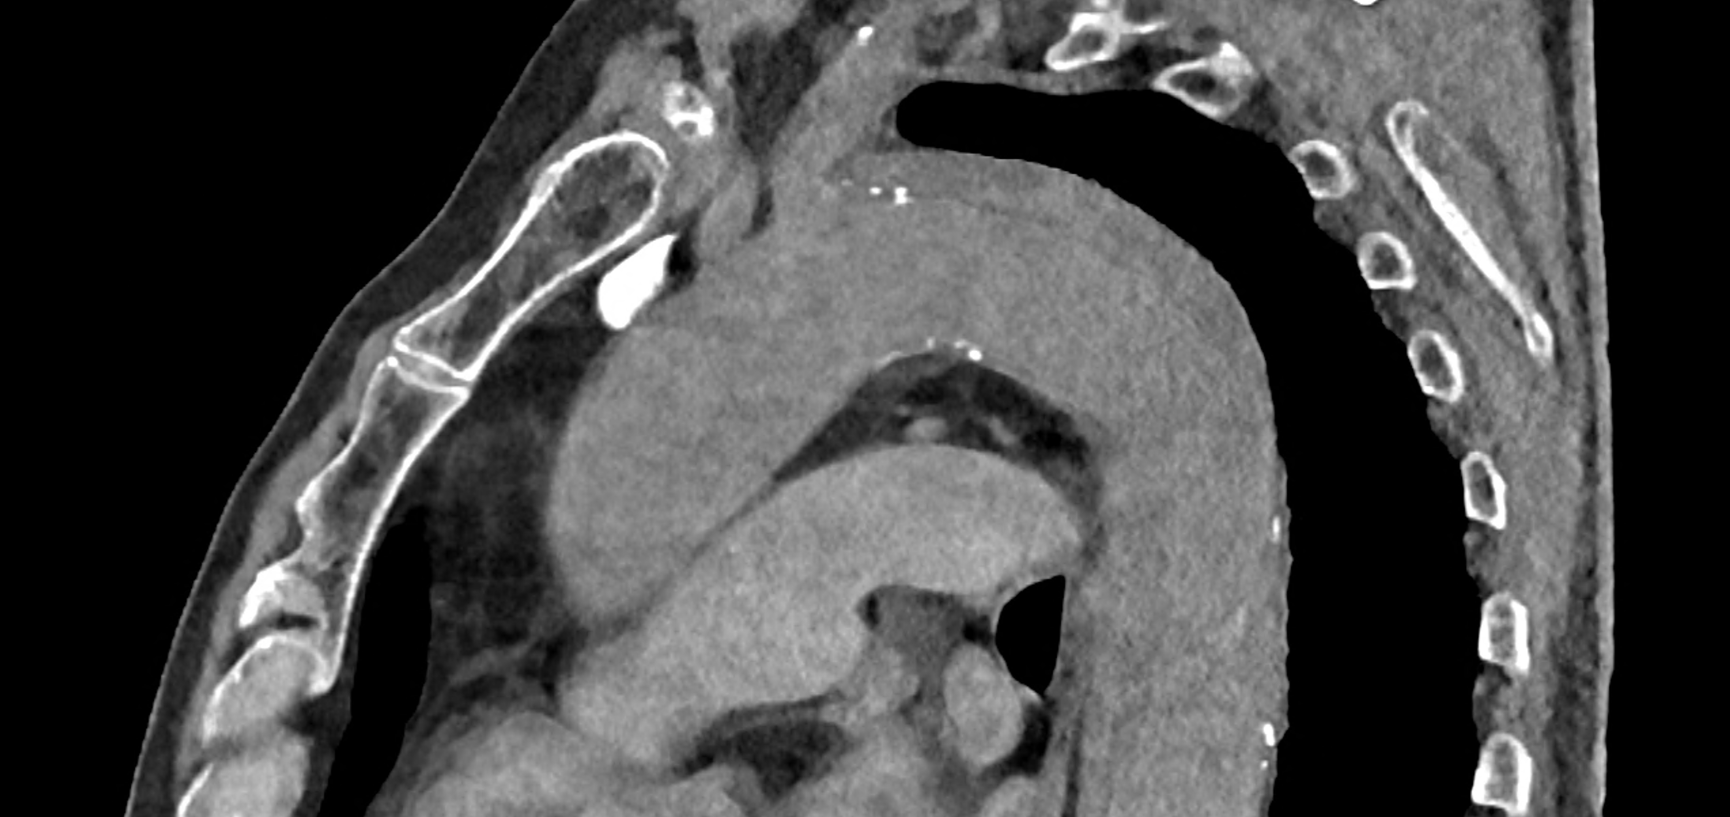

in patient chest pain, negative ECG but with elevated D-dimers was performed CTA of the chest to exclude highly suspected pulmonary embolism. No pulmonary embolism was see, but the pathology of the aortic arch and descending thoracic atorta. The images were consistent with aortic intramural hematoma type B according to the Stanford classification with incipient transformation in dissection – behind the subclavian artery, it is clear that the contrast agent is flowing into the intramural hematoma. Differentiation from wall thrombosis is facilitated by the presence of calcification in the detached intima, which is most clearly visible on virtual non-contrast imaging. The intramural hematoma itself exhibits different properties in terms of X-ray absorption. Coagulated blood is visible at the apex of the aortic arch, where it closely adjoins the area that is perfused and filled with contrast medium. There are other smaller areas filled with contrast medium at the sites of the intercostal arteries. These areas are secondary sites where the original intramural hematoma is channeled during its transformation into a classic aortic dissection.

Virtual non-contrast images help to distinguish between the intima and thus in the differential diagnosis of intramural hematoma versus wall thrombosis. Signs of fresh coagulated blood in IMH indicate bleeding into the aortic wall from the vasa vasorum. In contrast, monoenergetic images with lower energies of 40-55 keV highlight areas of intramural hematoma with active blood flow.

comparison of the the images 60, keV monoenergetic, virtual non-contrast (VNC), and iodine map images. The repercussion starts in the proximal tear of the intimate (the first three images), calcification in the intimate (next three images), tera at the level of the arising intercostal artery (last three images)

comparison of the sagittal aortic MPR in 40, 60, 140 and 190 keV monoenergetic images